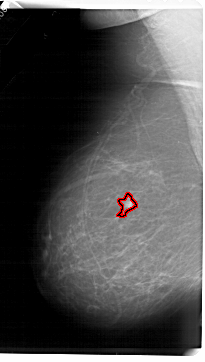

A_1665_1.LEFT_MLO

LEFT_MLO LINES 6871 PIXELS_PER_LINE 3886 BITS_PER_PIXEL 12 RESOLUTION 43.5 OVERLAY

FILE: A_1665_1.LEFT_MLO.OVERLAY

TOTAL_ABNORMALITIES 1

ABNORMALITY 1

LESION_TYPE MASS SHAPE IRREGULAR MARGINS ILL_DEFINED

ASSESSMENT 4

SUBTLETY 4

PATHOLOGY MALIGNANT

TOTAL_OUTLINES 1

BOUNDARY